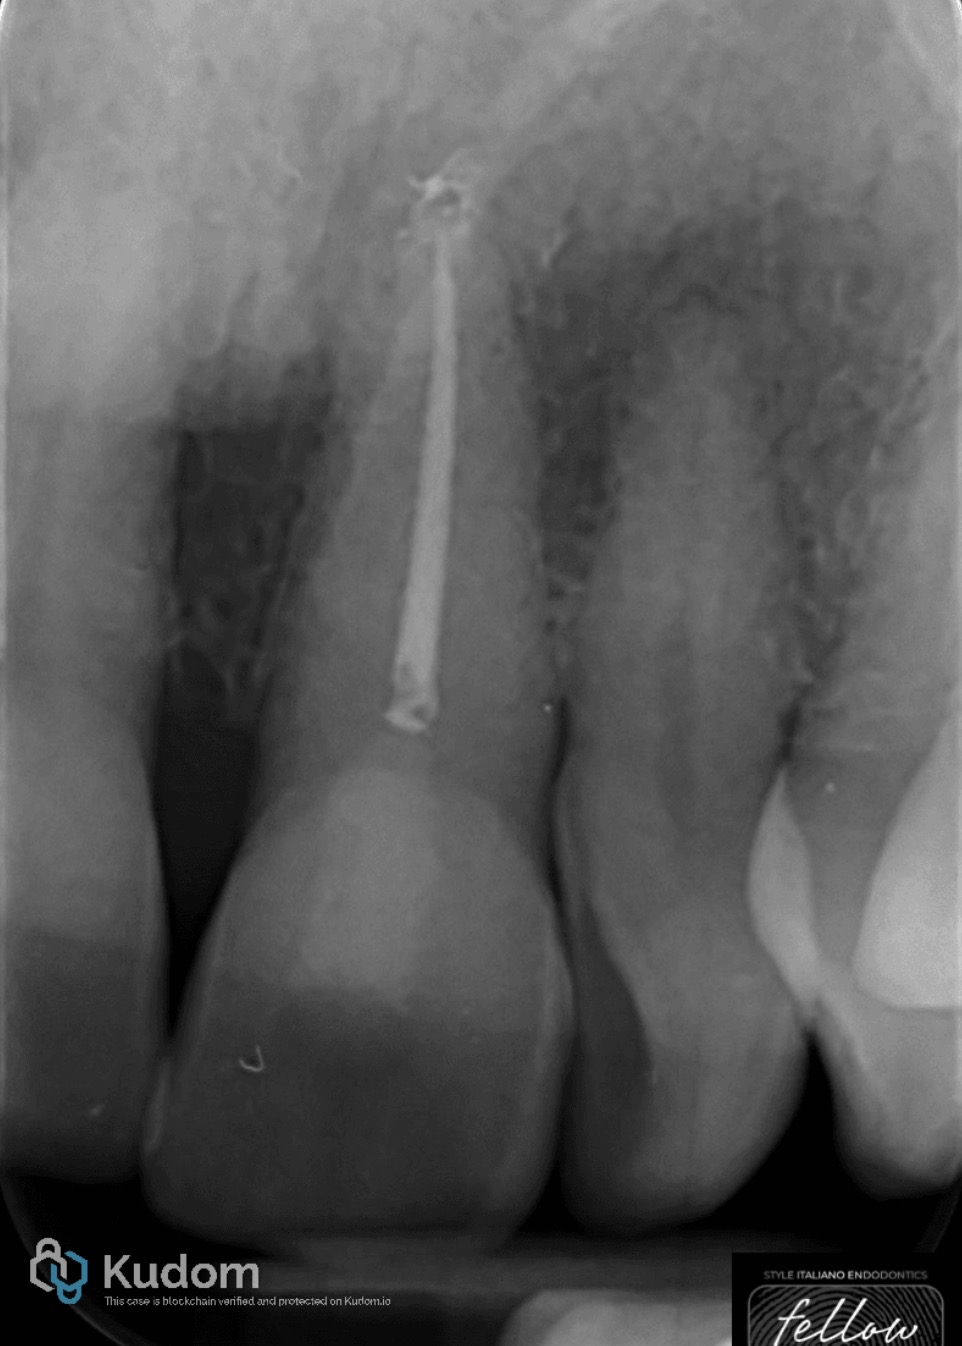

Fig. 3

Canal obturation was completed using a single-cone technique in combination with a bioceramic sealer.